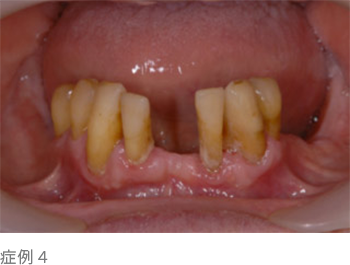

上の写真のように歯と歯の隙間が広くなったり、歯があらぬ方向に動き出し、出っ歯になったりもします。

この状態のまま放置してしまうと、ついには歯を失うことになってしまうのです。

歯を失うという事は、歯の周りの骨が大きく喪失し、顔の表情にも大きな変化をもたらします(写真下)。